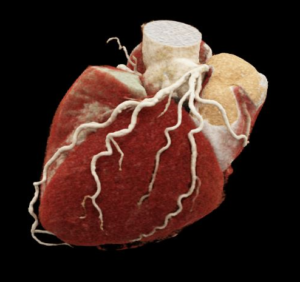

Coronary anatomy

Coronary arteries supply blood to the heart muscle itself. They are the first branches attached to the main artery which leaves the heart- the aorta- and sit like a crown on the heart’s surface hence the name coronary. There are two main arteries the left and the right each of which have numerous branches. The left coronary artery has two main branches – the left anterior descending (LAD) which goes down the front of the heart and the left circumflex (LCX) which travels around the back (posterior) of the heart. The right coronary artery travels on the right hand side and goes to the underside of the heart (inferior). Healthy arteries have considerable reserve capacity and symptoms of inadequate blood supply usually only occur when the diameter of an artery is reduced by 70% or more.

Normal coronary arteries

There are variations in normal coronary anatomy which are often harmless but in some cases the unusual course they take can cause problems such as when the coronary artery passes between the two arteries which leave the heart – the aorta and pulmonary artery.